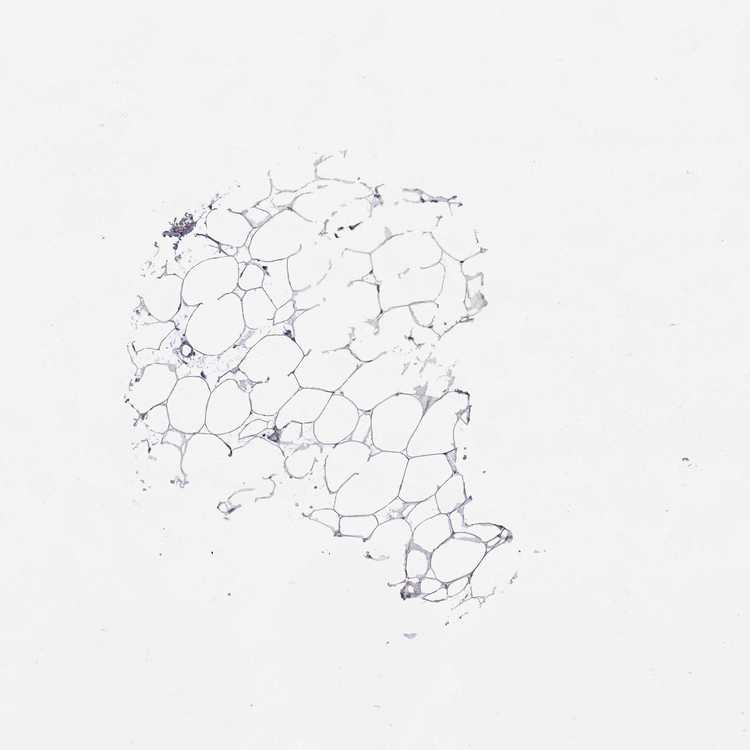

BREAST - Antibody stainingi

Antibody staining in the annotated cell types in the current human tissue is reported as not detected, low, medium, or high, based on conventional immunohistochemistry profiling in selected tissues. This score is based on the combination of the staining intensity and fraction of stained cells.

Each image is clickable and will lead to virtual microscopy that enables deeper exploration of all samples and also displays staining intensity scores, fraction scores and subcellular localization as well as patient and tissue information for each sample.

Antibody HPA011273Antibody HPA073244

Adipocytes Not detectedNot detected

Glandular cells LowNot detected

Myoepithelial cells Not detectedNot detected